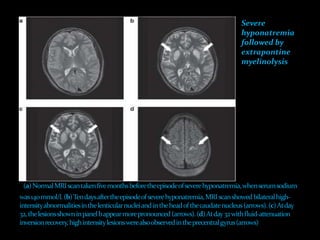

Severe

hyponatremia

followed by

extrapontine

myelinolysis

 The lesions of ODS classically affect the pons

 Clinically, patients with central pontine myelinolysis can present

one or more days after overcorrection of hyponatremia with

para- or quadraparesis, dysphagia, dysarthria, diplopia, a

"locked-in syndrome," and/or loss of consciousness.

 Other regions of the brain also can be involved in ODS.

 In order of frequency, the lesions of extrapontine myelinolysis

can occur in the cerebellum, lateral geniculate body, thalamus,

putamen, and cerebral cortex or subcortex.

 Development of ataxia, mutism, parkinsonism, dystonia,

and catatonia is seen in these